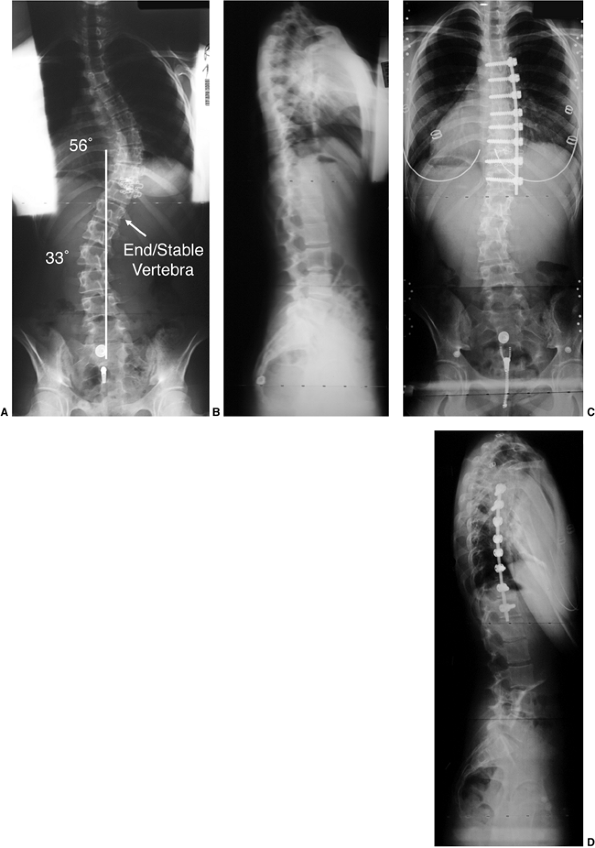

![]()  |

Figure 18.4 A: This posteroanterior radiograph demonstrates the appearance of a double thoracic scoliosis curve pattern. B:

The lateral radiograph demonstrates the relatively straight sagittal profile of the thoracic spine with loss of normal thoracic kyphosis. This is a common feature of adolescent idiopathic scoliosis. C: The clinical appearance of this patient demonstrates a prominent scapula. However, this is not caused by kyphosis but by the rotational deformity of the ribs, which secondarily makes the right scapula more prominent. Additionally, a left upper thoracic trapezial fullness can be appreciated in this patient, caused by the left upper thoracic curvature.  |